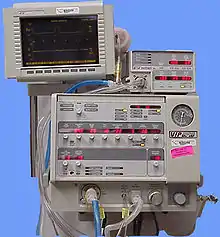

Type 1 respiratory failure may require oxygen therapy to achieve adequate oxygen saturation.[17] Lack of oxygen response may indicate other modalities such as heated humidified high-flow therapy, continuous positive airway pressure or (if severe) endotracheal intubation and mechanical ventilation. .

Type 2 respiratory failure often requires non-invasive ventilation (NIV) unless medical therapy can improve the situation.[18] Mechanical ventilation is sometimes indicated immediately or otherwise if NIV fails.[18] Respiratory stimulants such as doxapram are now rarely used.[19]

There is tentative evidence that in those with respiratory failure identified before arrival in hospital, continuous positive airway pressure can be helpful when started before conveying to hospital.[20]